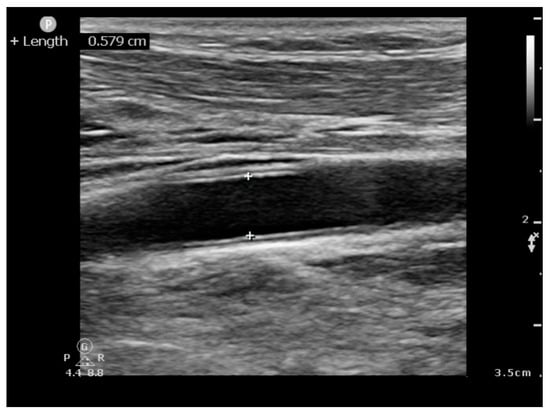

- CCA Area—Common Carotid Artery Area = D2 × 0.785.